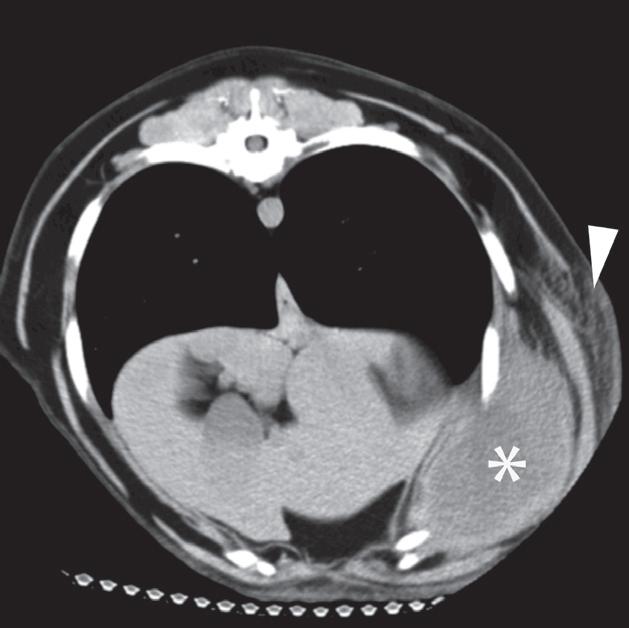

Badanie wykonano u 6-letniego, kastrowanego golden retrievera z fluktującą masą po lewej stronie w dobrzusznej części ściany klatki piersiowej. Radiogram grzbietowo-brzuszny (DV) klatki piersiowej uwidocznił dużą masę miękkotkankową wystającą z lewej ściany klatki piersiowej (a). Duża, jajowata masa jest widoczna na lewej brzusznej ścianie powłok. Jest ona głęboko położona w stosunku do zewnętrznych mięśni skośnych brzucha i wkracza przyśrodkowo do krawędzi żeber (b, c – gwiazdka). Część centralna ma około 15 HU zarówno na niewzmocnionych, jak i wzmocnionych obrazach TK (b, c), a masa ma gruby, obwodowo wzmacniający się rąbek (c). Widać również objawy bardziej powierzchownego, rozlanego zapalenia tkanki łącznej (cellulitis) (b, c – grot strzałki). Masę usunięto chirurgicznie i potwierdzono, że zawierała materiał ropny